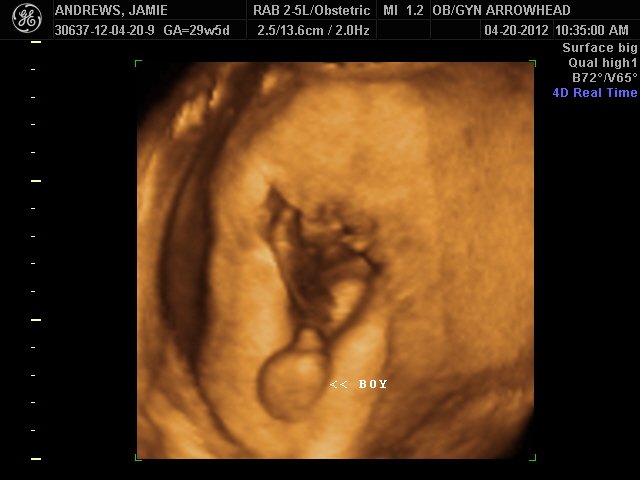

We offer complimentary 3D/4D Ultrasounds to all our OB patients around 30 weeks! The following photos are some examples of our work, shown with permission from our patients.